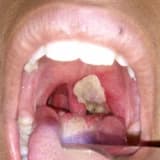

Öd yollarının xərçəngləri (xolenjiokarsinoma)

Öd yollarında meydana gəldiyi yerə görə xərçəngləri müxtəlif növlərə ayırırlar:

İntrahepatik xolangiokarsinoma qaraciyər daxilindəki safra yollarının hissələrində baş verir və bəzən qaraciyər xərçənginin bir növü kimi təsnif edilir.

Hilar xolangiokarsinoma qaraciyərdən kənarda olan safra yollarında baş verir. Bu tipə perihilar xolangiokarsinoma da deyilir.

Distal xolangiokarsinoma öd axarının nazik bağırsağa ən yaxın hissəsində baş verir.